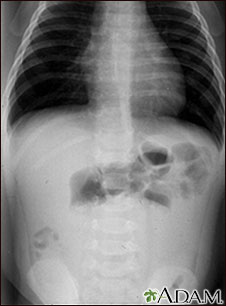

This abdominal x-ray shows an intestinal condition in which a loop of bowel has slipped into another section of bowel (intussusception), causing swelling, reduced blood flow, obstruction, and tissue damage. Intussusception requires emergency treatment (barium enema or surgery) to prevent intestinal tissue death (necrosis), intestinal perforation, peritonitis, and death.